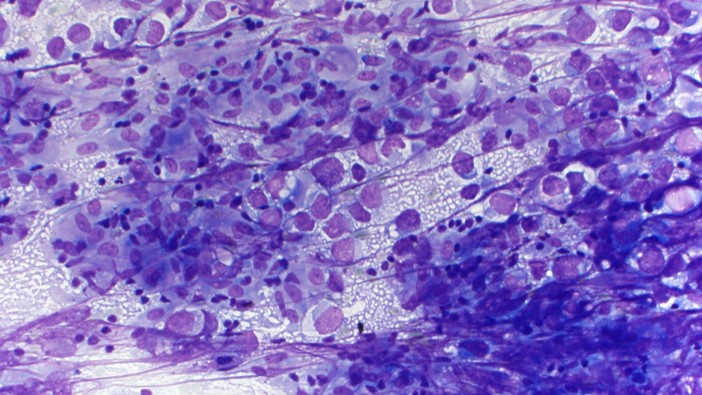

The specimen is cellular and consists of abundant large and dyshesive cells with somewhat rhabdoid/plasmacytoid morphology, prominent nucleoli, and moderate amounts of vacuolated cytoplasm. In the background there are small lymphocytes and a focal bubbly/tigroid appearance, as well as non-necrotizing granulomas.

Immunohistochemical stains were performed on this case. The cells were positive for OCT3/4 and SALL4, and negative for cytokeratin cocktail, SOX10, INI1 (retained), and SMARCA4 (retained). Together with the morphology, this staining pattern is consistent with germ cell neoplasm.